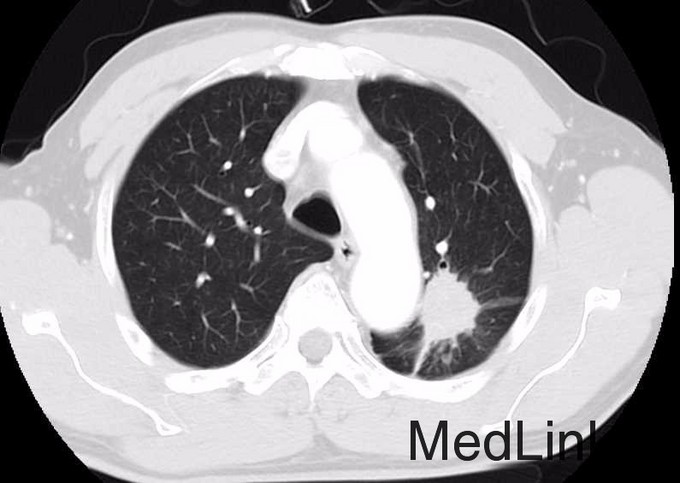

胸部CT:左上肺占位性病变,直径约4cm,边界不清,伴周围胸膜挛缩,无纵膈淋巴结肿大